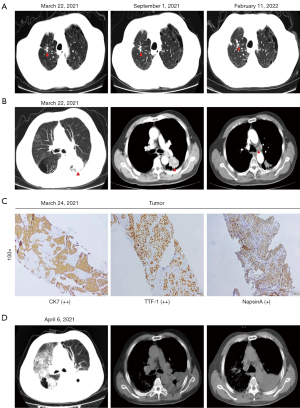

An 81-year-old male presented at the end of January 2021 with an irritating cough, blood in the sputum, night sweats and malaise, but no fever. He had a >40-year history of smoking 10 cigarettes/day and had quit smoking 5 years earlier. The patient had a 10-year history of diabetes mellitus and contracted tuberculosis over 20 years earlier (Figure 1A). An enhanced chest CT scan was performed at our hospital on Mar 22, 2021, which showed a mass of approximately 48 mm ×42 mm in the dorsal segment of the lower lobe of the left lung, with moderate heterogeneous enhancement (Figure 1B). A left lung puncture biopsy was performed under ultrasound guidance at our hospital on Mar 23, 2021. Biopsy pathology (K202113002) for NSCLC was performed on Mar 24, 2021, and the immunohistochemistry analysis (IHC202101714) of the left lung puncture specimen revealed adenocarcinoma. The immunohistochemistry marker results were as follows: tumor cells p40 (−), p63 (−/+), CK5/6 (−), CK7 (2+), Napsin A (+), TIF-1 (2+), CD56 (−), Syn (−), CgA (−), and Ki-67 (2+, approximately 70%) (Figure 1C). MRI of the head was performed on Mar 26, 2021 and showed no brain metastasis; on Apr 01, 2021, the NGS genetic test results revealed MET copy number amplification. Targeted therapy with crizotinib (250 mg bid) was initiated on Apr 02, 2021. The patient complained of recurrent fever on Apr 04, 2021. A chest enhanced CT scan was performed on Apr 06, 2021 and showed a pulmonary infection (Figure 1D). On Apr 07, 2021, oral crizotinib targeted therapy was suspended, and the patient was prescribed cefoperazone sodium sulbactam sodium and continued anti-inflammatory treatment. After the patient’s fever improved, oral crizotinib was resumed.